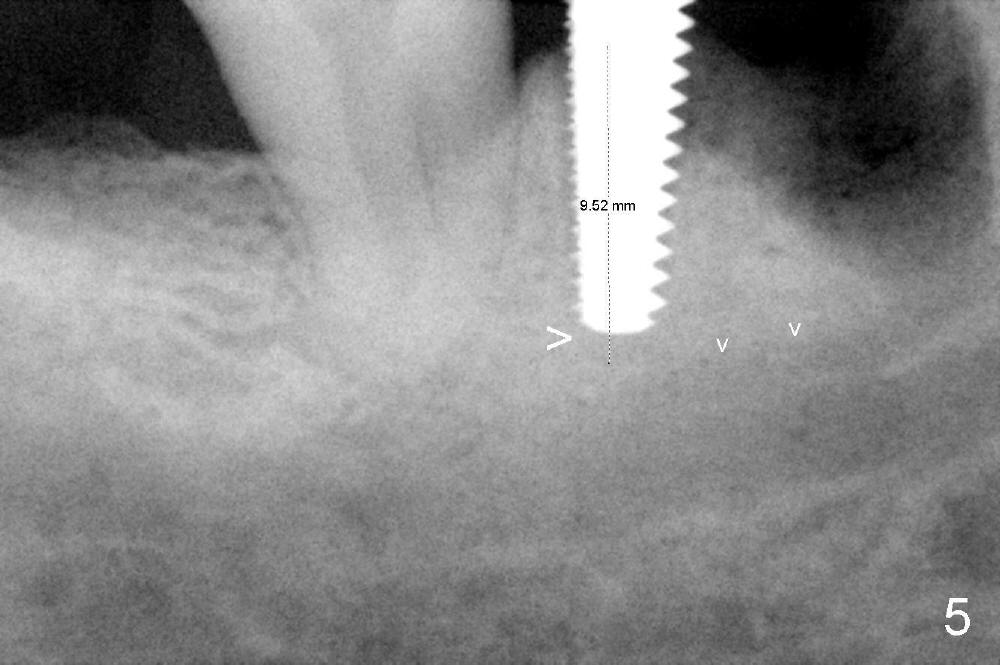

As to where to place an implant, we try to engage the largest tap (8 mm in diameter) into the mesial socket without binding. The buccal plate of the mesial socket is missing.  It is risky to extend osteotomy in the mesial socket.  Besides, the septum (Fig. 4 S) is not as tall as the distal socket (D).  It appears that the distal socket is the safest place to place an implant.  Furthermore, no drill is used for distal osteotomy.  Instead two osteotomes (3.5x15 and 4x15 mm tapered osteotomes) are used to expand the distal socket with intention to push the septum mesially.  Since the bone density is high, the osteotomes seem not to work as effectively as expected.  Then a 4.5x17 mm tap is placed at the depth ~ 14 mm with stability (Fig.5).  Finally a 5x14 mm tissue-level implant is placed with insertion torque >60 Ncm (Fig.6).  Allograft is placed in the mesial socket and buccal aspect of the distal socket, followed by insertion of collagen plug and membrane (Fig.7).  After insertion of an abutment (Fig.8 (taken 6 days postop) *), perio dressing (P) is applied to cover the wound.  There is no postop paresthesia.